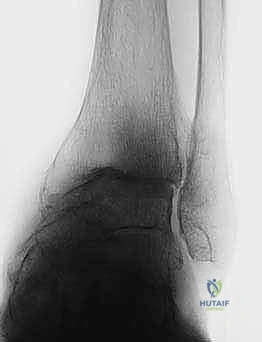

الأسباب العميقة وعوامل الخطر لخشونة الكاحل المتقدمة

على عكس مفصلي الركبة والورك، حيث تكون الخشونة الأولية (بسبب التقدم في العمر والاستهلاك الطبيعي) هي السبب الشائع، فإن خشونة مفصل الكاحل لها طبيعة مختلفة تماماً. الغالبية العظمى من حالات تآكل مفصل الكاحل هي نتيجة لإصابات سابقة أو أمراض جهازية.

1. خشونة الكاحل ما بعد الصدمة (Post-Traumatic Osteoarthritis)

يمثل هذا النوع حوالي 70% إلى 80% من جميع حالات خشونة الكاحل. يحدث عندما يتعرض المفصل لإصابة تؤدي إلى تلف ميكانيكي مباشر للغضروف أو تغير في استقامة العظام.

* كسور الكاحل المعقدة: الكسور التي تشمل السطح المفصلي (Pilon fractures أو Malleolar fractures) تترك ندبات على الغضروف وتغير من توزيع الوزن.

الأعراض السريرية: متى يجب التفكير في الجراحة؟

التشخيص الدقيق: نهج الأستاذ الدكتور محمد هطيف

يبدأ التقييم الطبي الشامل بأخذ تاريخ مرضي دقيق وفحص سريري مفصل. يقوم الدكتور هطيف بتقييم نطاق الحركة، قوة العضلات، استقامة القدم والكاحل، وحالة الدورة الدموية والأعصاب الطرفية.

تُعد الأمانة الطبية الصارمة ركيزة أساسية في ممارسة الدكتور هطيف؛ فهو لا يتخذ قرار الجراحة إلا بعد استنفاد كافة سبل التقييم الدقيق. يعتمد التشخيص على أحدث تقنيات التصوير الطبي:

* الأشعة السينية أثناء الوقوف (Weight-bearing X-rays): هي المعيار الذهبي لتقييم تضيق المسافة المفصلية، وجود النتوءات العظمية، وتحديد درجة التشوه (Varus/Valgus).